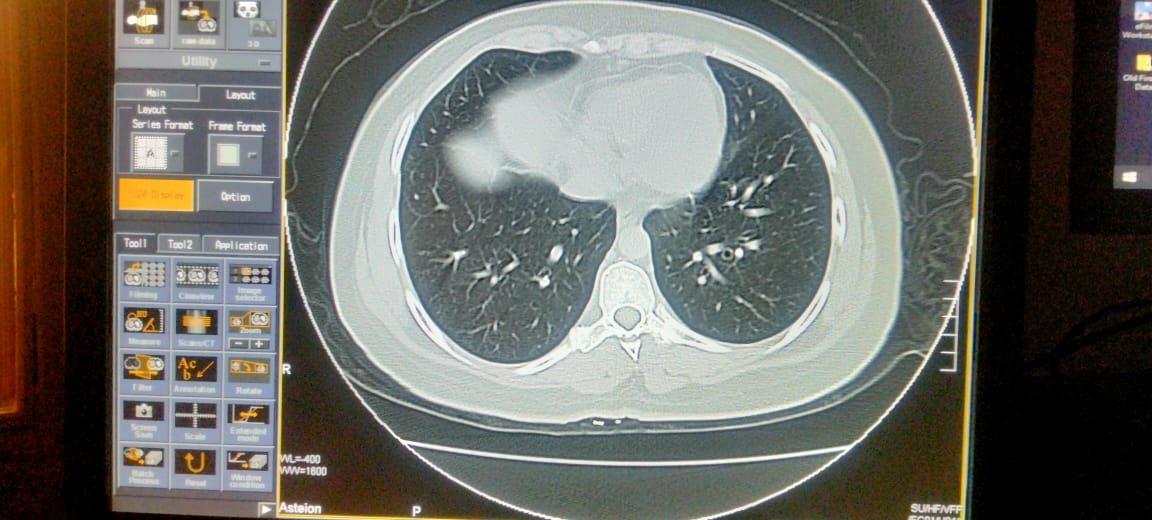

Plz describe it. Film of hrct of corona patient

Send full films, its incomplete